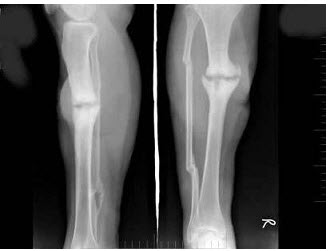

22、单项选择题

女,48岁,车祸致右胫腓骨骨折,外固定术后两年复查,如图所示,最可能的诊断是()

A.右胫骨愈合延迟

B.右胫骨假关节形成